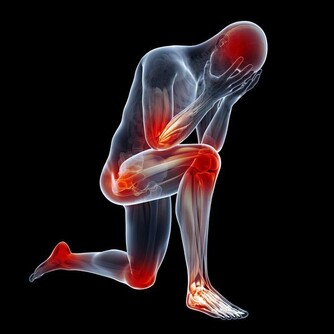

但重要的是,你要意識到自己的尿頻可能意味著更嚴重的可能性,特別是如果你正在經歷卵巢癌的其他常見症狀,如腹脹、食慾減退或骨盆和/或腹痛。如果你的尿頻與任何這些症狀同時出現,最好盡快看醫生。